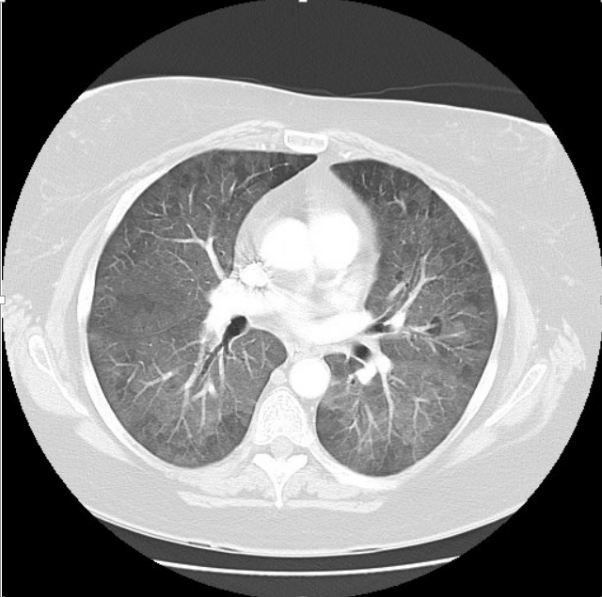

Figure. CT scan chest

You then send the patient for a CT scan of the chest. A representative image is shown at right, above (please click image to enlarge).

Note the diffuse increased ground glass opacities throughout both lung fields. In addition, there are areas of relative sparing bilaterally as well, representing air trapping in the small airways. If expiratory films were obtained, these areas would become more pronounced, confirming this finding.